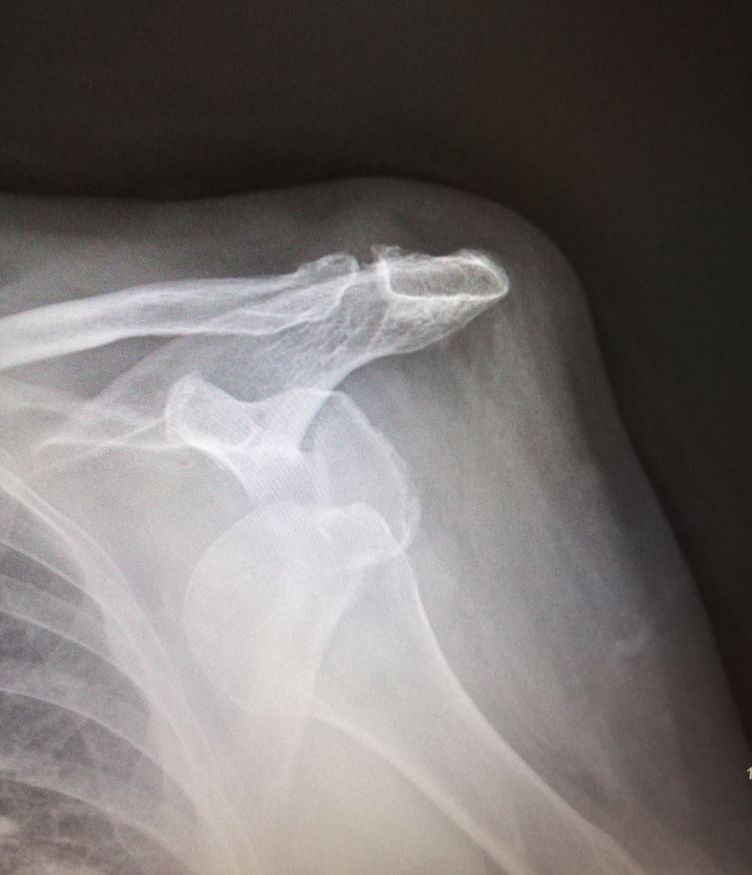

Little luxation after lady fell down from bed

Shoulder dislocation